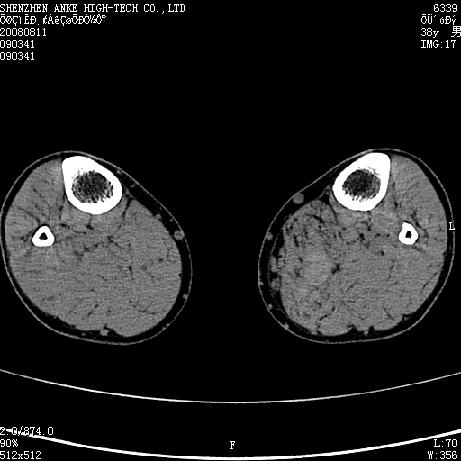

标题: CT15117:M38Y,小腿平扫 [打印本页]

标题: CT15117:M38Y,小腿平扫

患者,男,38岁,右小腿疼痛性包块1月,查体:右小腿可扪及约5x4cm大小包块,压痛.

左小腿内侧软组织病变,性质待定(血管瘤?);建议行mri检查。